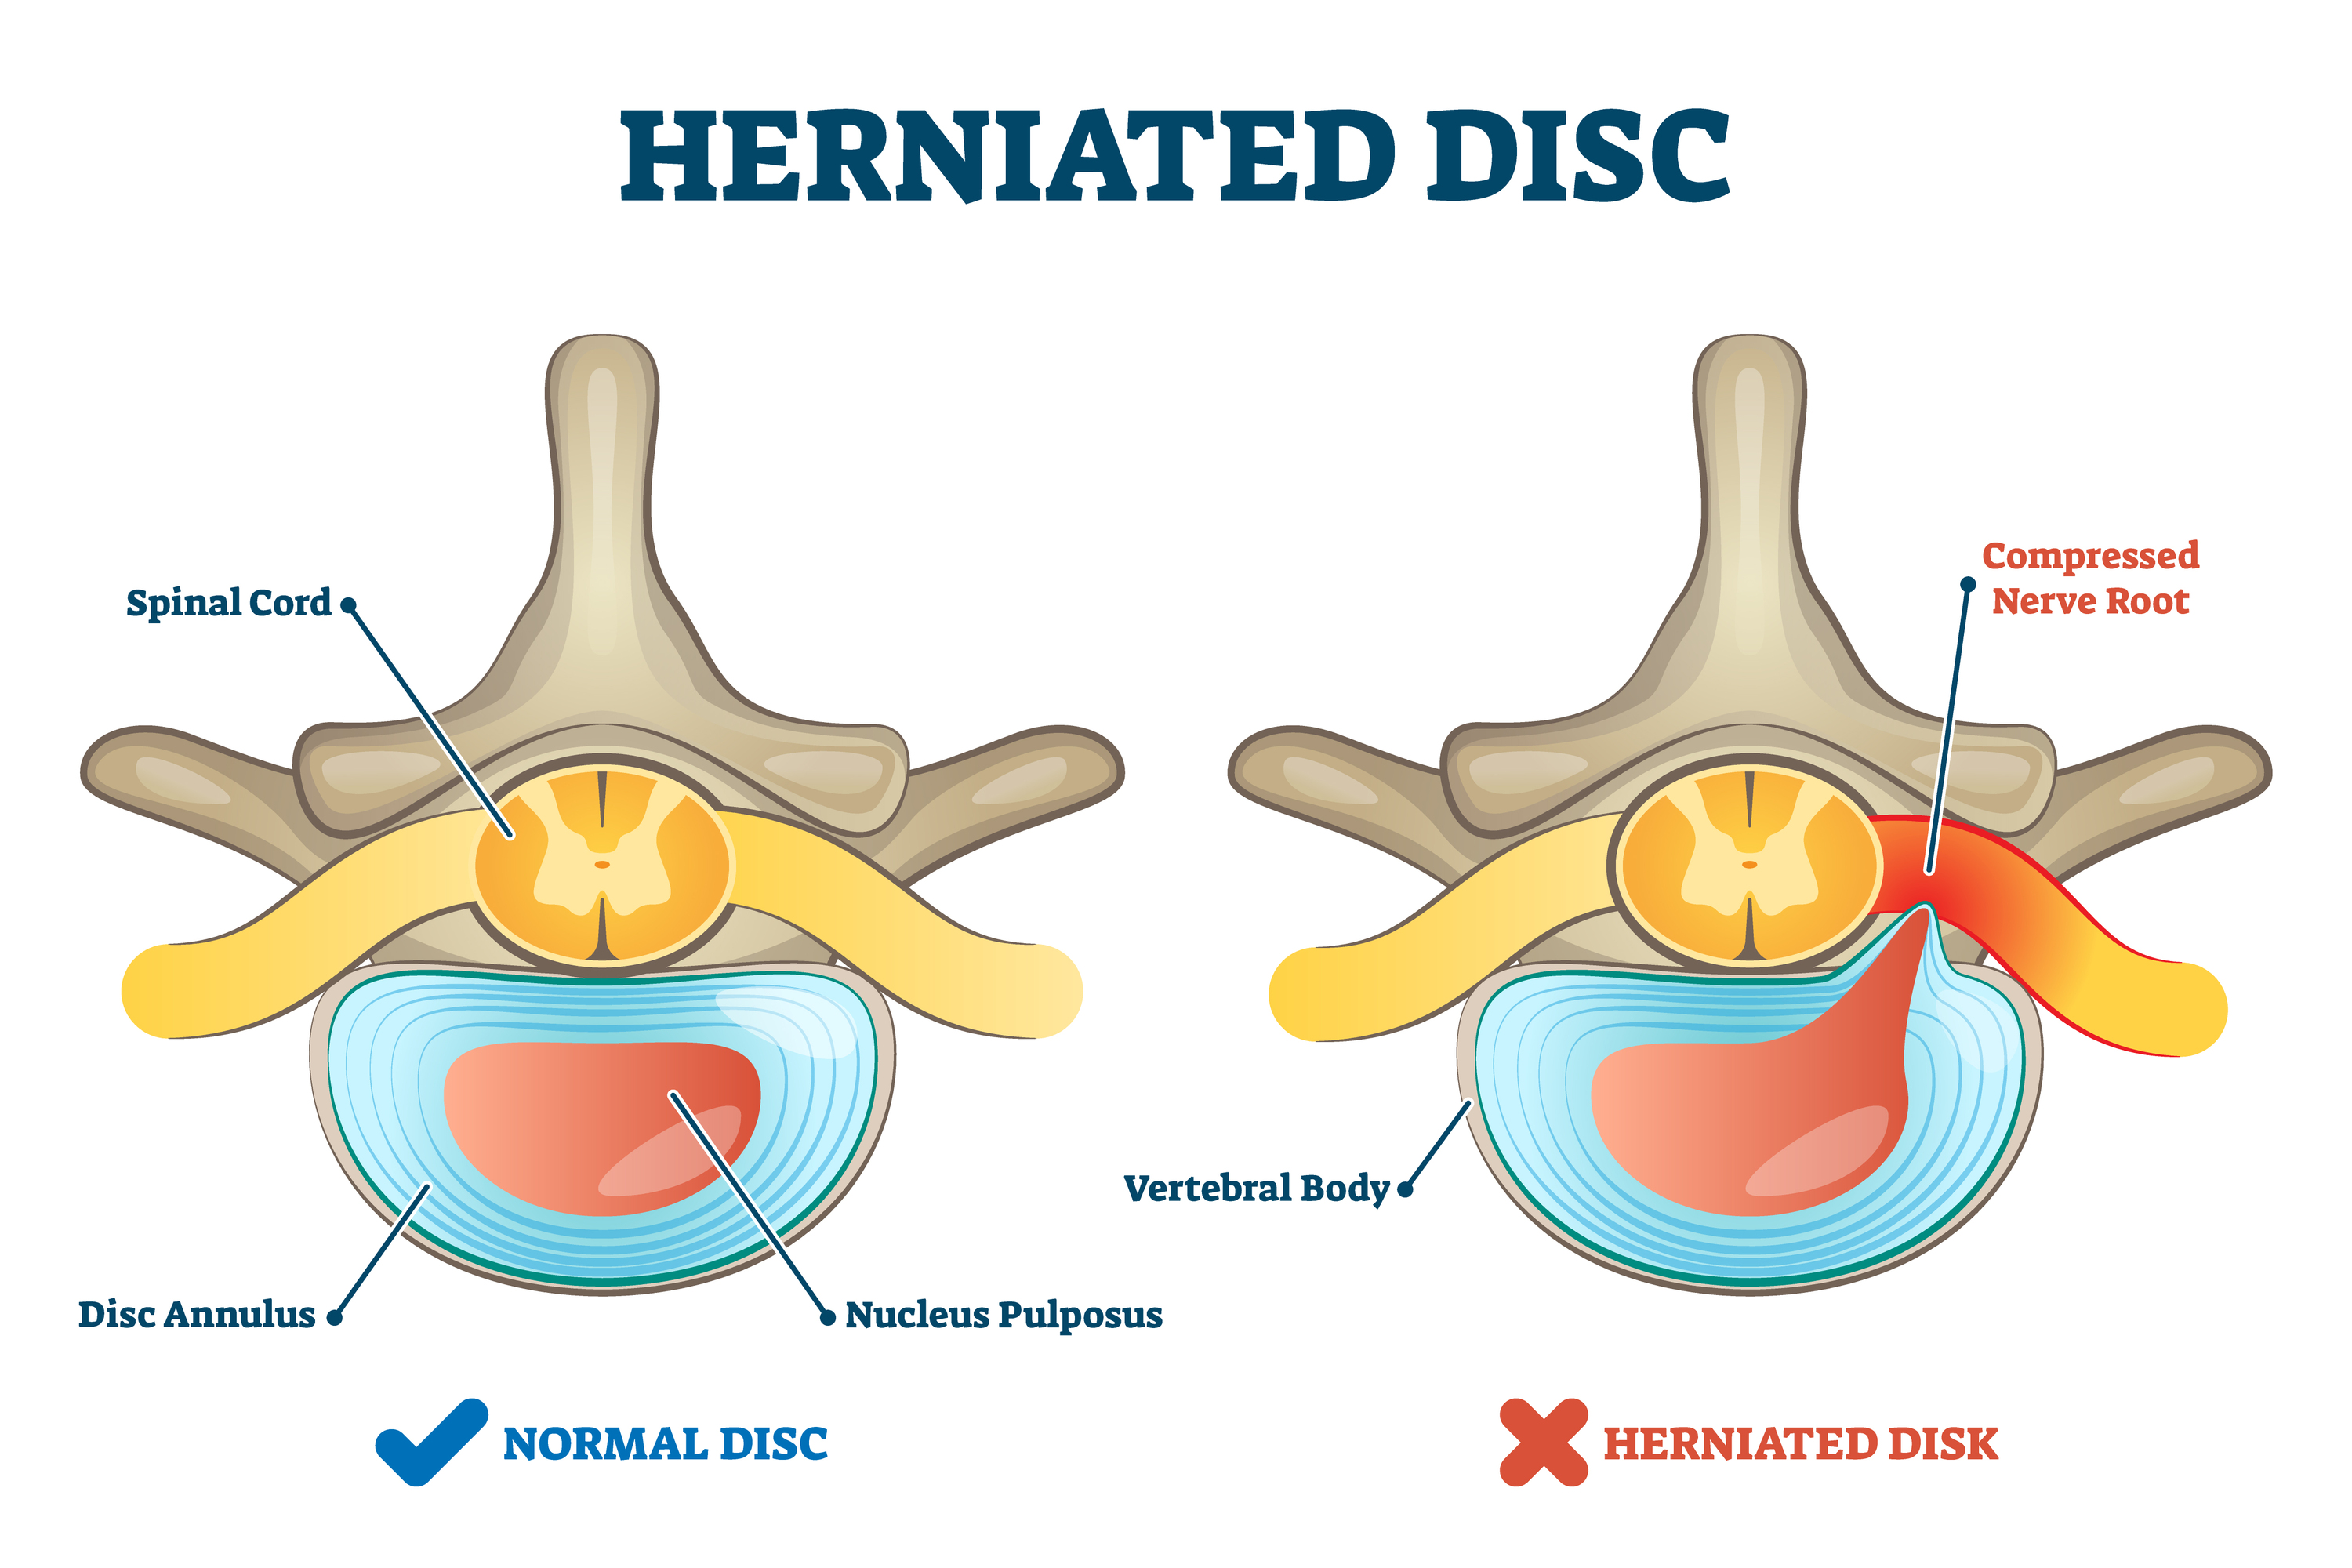

In some cases of degeneration, the nucleus of the disc may push through a torn annulus, toward or into the spinal canal, or into the space where the spinal nerves are located. This is called a herniated or ruptured disc. Sometimes patients refer to this as a slipped disc. The disc material that squeezes out may directly press against the spinal nerves. The disc tissue that pushes through also releases enzymes and chemicals that produce inflammation in the area. The inflammation caused by the chemicals released from the disc often, but not always, causes the transfer of pain signals to the brain. Pressure on the nerves may cause additional sensitization or breakdown of the protective sheath around the nerves.

Herniated Disc

A weakened disc may herniate (shift out of place) or eventually rupture. If the annulus of the disc tears or ruptures, the material in the nucleus can squeeze out of the disc or herniate. A disc may herniate a little or a lot, and the symptoms will vary accordingly. A disc herniation usually causes compressive problems if the disc presses against a spinal nerve. The chemicals released by the disc may also inflame the nerve root, causing pain in the area the nerve travels to such as the pelvis, lower back, or legs. If this type of pain travels down the back of the leg, it may be referred to as sciatica.

Disc herniation occurs more often in younger populations (20-50 years old) when the disc is plump and well hydrated. Poor mechanics while lifting heavy objects or making repetitive movements (bending, twisting, and lifting) can place too much pressure on the disc. The increased pressure can cause the annulus to tear and the nucleus to rupture into the spinal canal.